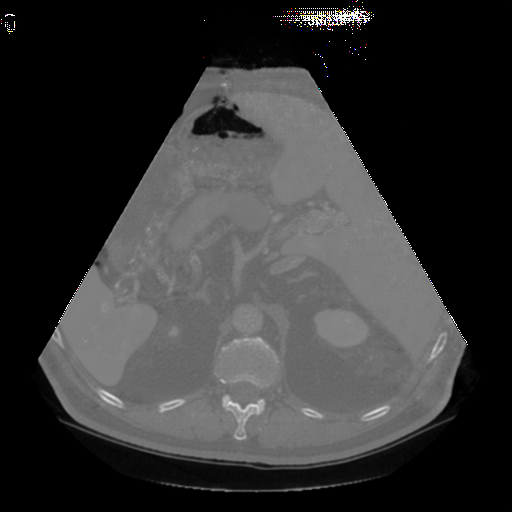

The Abdomen-1K dataset provides more than 1000 CT scans, and the data is provided in 3D format. Firstly, we randomly select 200 CT scans, and for each CT scan, we randomly sampled 10 transverse plane slices. For a more uniform image shape, we applied a fan shape mask to the CT images to mimic the outline of convex ultrasound images.

Fig. 5 and 6 present examples of the translation results from CT to ultrasound. These visual comparisons demonstrate that the S-CycleGAN can not only mimic the ultrasound style but also preserve critical anatomical features compared with Fig. 3. The synthetic images closely resemble real ultrasound scans in terms of texture and shape, suggesting a high level of detail preservation.

Refer to caption

(a) Real CT

(b) Fake US

(c) CT Label

(d) Predicted US Mask

Figure 6: CT-to-ultrasound translation example.2